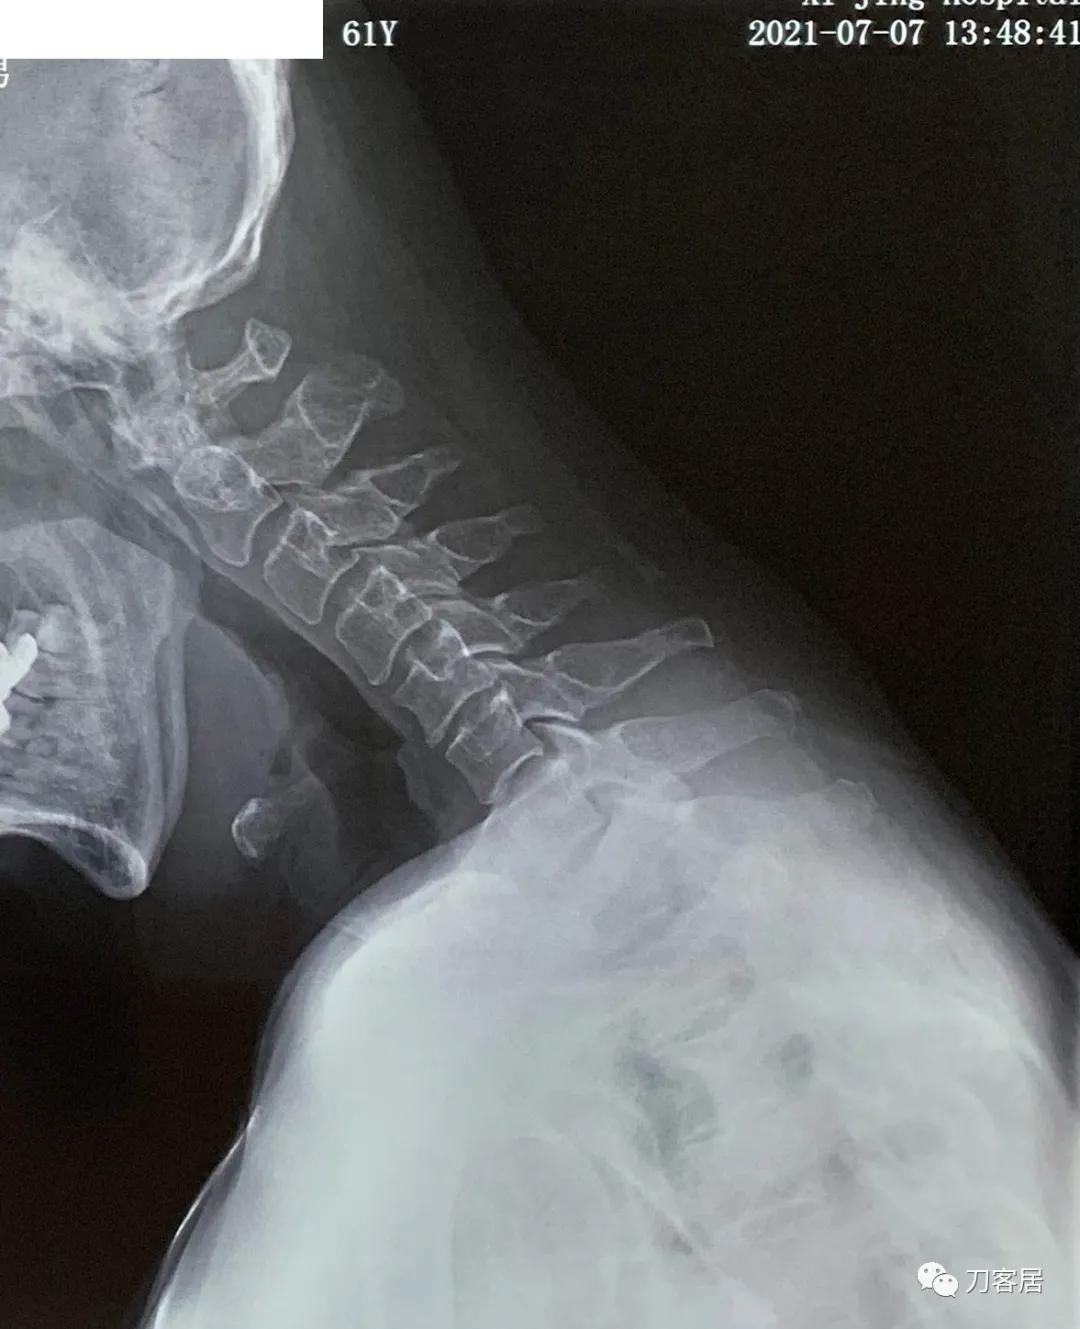

图9. 20210721颈椎过伸侧位X线片